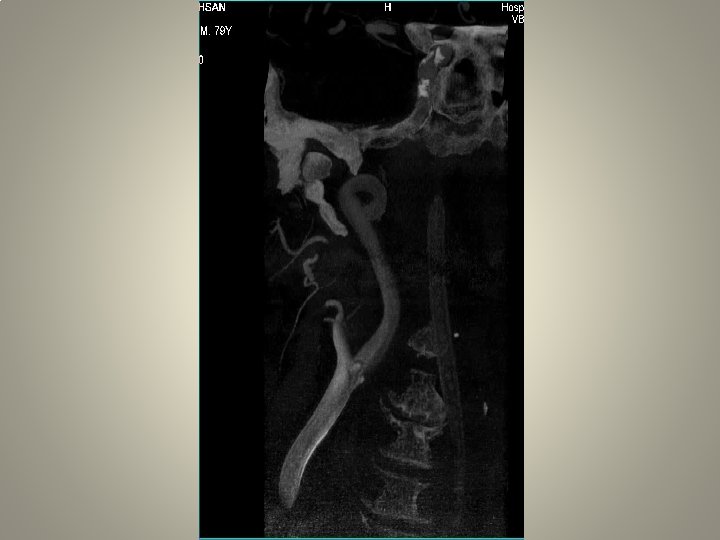

pre-op • • • Karotis stentleme için uygun hazırlık önemli Anti-agregan kullanımı Hassasiyet ölçümü diffüzyon MR: yeni lezyon? İşlem sırasında sedasyon ağrı duyulmasın Kan basıncı monitorizasyonu

Vasküler erişim • Kateterizasyon: uzun re-inforced sheats (terumo, arrow, cook) uzun diagnostik kateter 120/125 cm Hidrofilik (Terumo 0. 035 -38 stiff or roadrunner-Cook) teller Hidrofilik olmayan (amplatz) teller